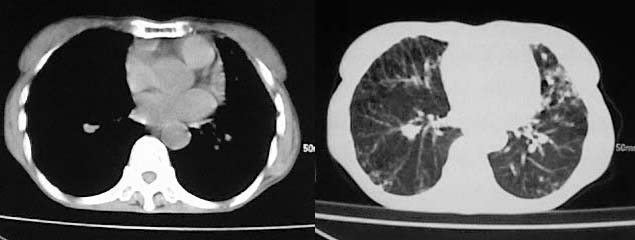

以下是引用zjzjr在2008-5-2 14:39:00的发言:[br]支持双侧继发型肺结核,左侧胸膜肥厚,慢性支气管炎伴间质纤维化.